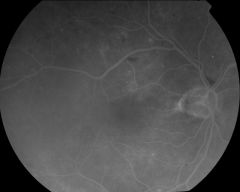

IM000031 |